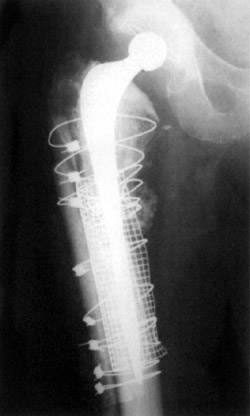

1. 2.

Figure 2. Allogran-N allograft impacted into femur.

The large defect in the cortex was surrounded with a stainless steel mesh and tension band wire through the linear aspira, leaving the soft tissue attachments in place as far as possible. Four allograft struts were applied to the outside of the femur sub-periosteally, and secured with a Dall-Miles cable system.

The femur was prepared proximally using the Exeter impaction grafting system, Allogran-N Hydroxyapatite and two femoral heads to take a 200mm Exeter prosthesis, with a single mix of CMW cement with Gentamycin.

Stable reduction was achieved with a neutral head. The remainder of the bone graft/Allogran-N composite was packed around the periosteal pouch at the fracture site posteriorly. Closure was achieved with vicryl and clips to the skin. One drain was placed.